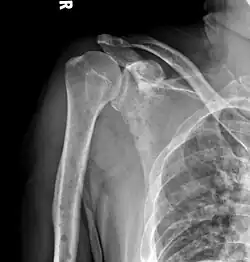

The diagnostic examination of a person with suspected multiple myeloma typically includes a skeletal survey. This is a series of X-rays of the skull, axial skeleton, and proximal long bones. Myeloma activity sometimes appears as "lytic lesions" (with local disappearance of normal bone due to resorption) or as "punched-out lesions" on the skull X-ray ("raindrop skull"). Lesions may also be sclerotic, which is seen as radiodense.[76] Overall, the radiodensity of myeloma is between −30 and 120 Hounsfield units (HU).[77] Magnetic resonance imaging is more sensitive than simple X-rays in the detection of lytic lesions. An MRI may supersede a skeletal survey, especially when vertebral disease is suspected. Occasionally, a CT scan is performed to measure the size of soft-tissue plasmacytomas. Nuclear Medicine Bone scans are typically not of any additional value in the workup of people with myeloma (no new bone formation; lytic lesions not well visualized on nuclear bone scan).

Skull X-ray showing multiple lucencies due to multiple myeloma -